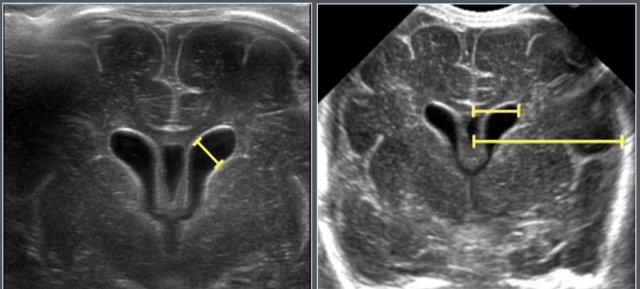

Não thất

Vật liệu và Phương pháp

Nghiên cứu siêu âm được thực hiện trên 1.483 trẻ sơ sinh (tuổi thai 25–42 tuần) được khám vào ngày thứ 3 sau sinh.

Các trẻ có tiền sử ngạt chu sinh, nhiễm trùng hệ thần kinh trung ương, xuất huyết nội sọ hoặc dị tật sọ-cột sống đã được loại trừ.

Các nguyên nhân thường gặp gây giãn não thất bao gồm

- Dị tật bẩm sinh (ví dụ: holoprosencephaly)

- Não úng thủy tắc nghẽn

- Não úng thủy thông thương

- Teo não

Các chỉ số đo

- Chiều rộng sừng trước (AHW)

- Tỷ số não thất-bán cầu (VHR)

Được đo trên các lát cắt mặt phẳng coronal ở mức lỗ Monro.